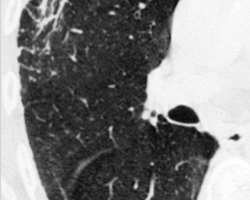

Femme de 65 ans

ATCD : tabagisme sevré, néo du sein droit traité par chirurgie et radiothérapie, exposition à l’amiante

Douleurs thoraciques droites + dyspnée d’effort + toux sèche

Abolition du murmure vésiculaire de la base droite + perte de poids